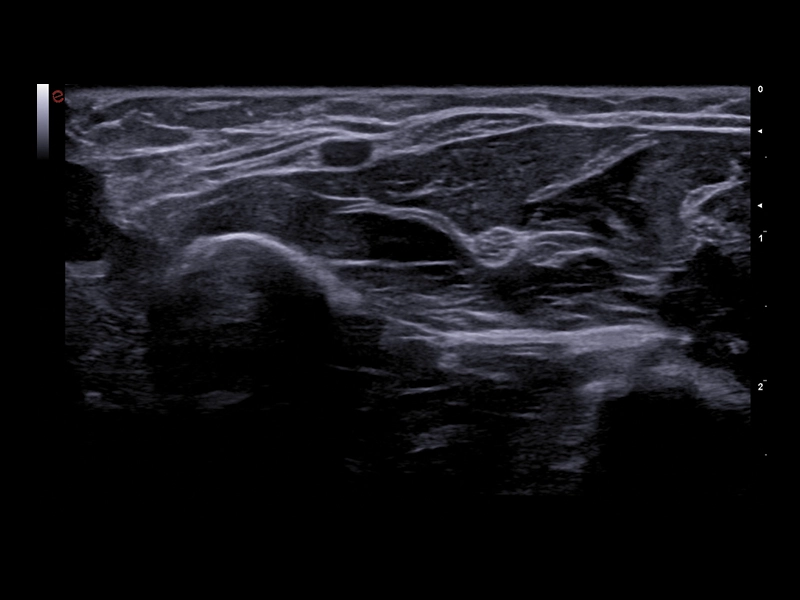

MyLab™E80 - LX 3-15 - B-Mode - MSK

MyLab™E80 - LX 3-15 - B-Mode - MSK

MyLab™E80 - microV - MSK

MyLab™E80 - microV - MSK

MyLab™E80 - B-Mode - Nerve

MyLab™E80 - B-Mode - Nerve

MyLab™E80 - B-Mode - MSK

MyLab™E80 - B-Mode - MSK